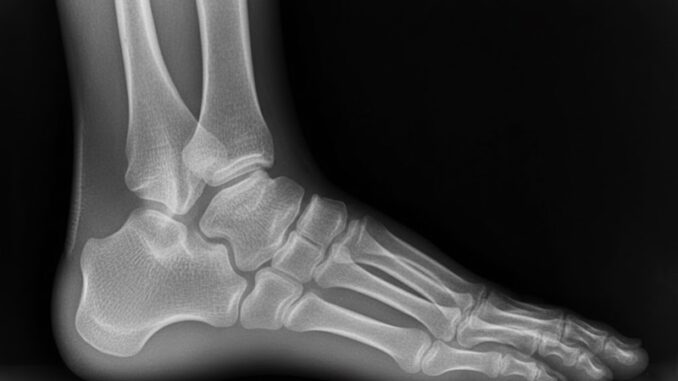

Varování: První příznak rakoviny kostí lidé zaměňují za artritidu! Kdy jít ihned k lékaři?

Rakovina kostí, i když je poměrně vzácným typem nádorového onemocnění, představuje vážnou zdravotní výzvu. Klíčovým faktorem pro úspěšnou léčbu je rozpoznání raných signálů, které bohužel bývají často přehlédnuty, protože se dají snadno zaměnit za běžné ortopedické potíže. Je proto nezbytné věnovat zvýšenou pozornost svému tělu a v případě pochybností se obrátit na odborníky.

Nejpřesvědčivějším a nejčastějším prvním příznakem, který naznačuje přítomnost zhoubného nádoru v kosti, je bolest. Zpočátku může být tato bolest jen mírná, přerušovaná a může být mylně připisována únavě, sportovnímu zranění nebo dokonce revmatickým stavům, jako je artritida. Nicméně, bolest spojená s rakovinou kostí má tendenci se s postupem nemoci měnit a zhoršovat.

Charakteristickým znakem, který odlišuje tuto bolest od většiny jiných, je její noční exacerbace. Zatímco při běžných zánětlivých a mechanických potížích přináší klid úlevu, pacienti s rakovinou kostí často uvádějí, že bolest je nejintenzivnější v noci, zejména když si lehnou ke spánku. Tato přetrvávající, zhoršující se noční bolest by měla být vždy červenou vlajkou vedoucí k okamžité lékařské prohlídce. Postupně se bolest stává trvalou a nereaguje na volně prodejné léky.